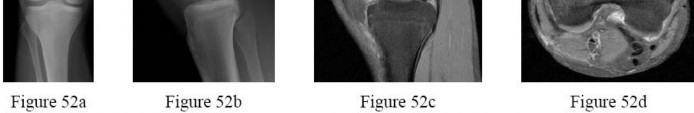

Question 10

A 55-year-old carpenter presents with right shoulder pain and weakness after attempting to lift a heavy tool box. On physical examination, he demonstrates a positive drop-arm test and profound weakness with active abduction in the scapular plane. An MRI confirms a massive, retracted tear of the supraspinatus and infraspinatus tendons. Fatty infiltration of these muscles is graded. Which classification system is most commonly used to grade fatty infiltration of the rotator cuff muscles on imaging?

Explanation

The Goutallier classification is used to quantify the amount of fatty infiltration of the rotator cuff muscles, originally described on CT but now widely adapted for MRI. High grades of fatty infiltration (Goutallier 3 and 4) are associated with poor functional outcomes and higher re-tear rates following surgical repair.